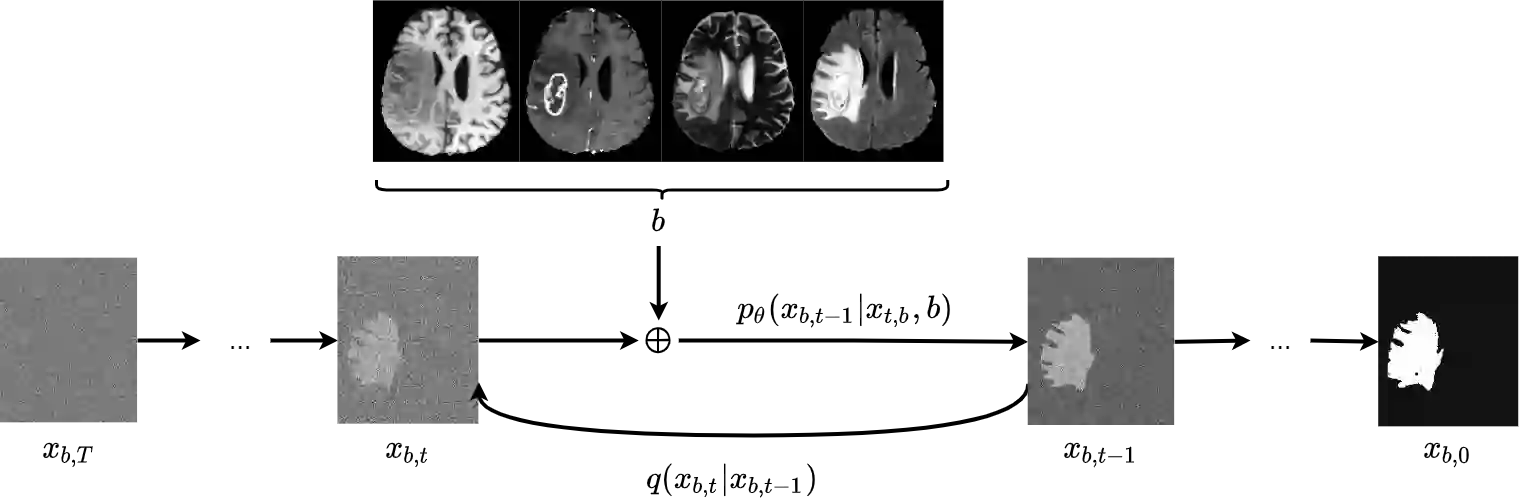

Diffusion models have shown impressive performance for generative modelling of images. In this paper, we present a novel semantic segmentation method based on diffusion models. By modifying the training and sampling scheme, we show that diffusion models can perform lesion segmentation of medical images. To generate an image specific segmentation, we train the model on the ground truth segmentation, and use the image as a prior during training and in every step during the sampling process. With the given stochastic sampling process, we can generate a distribution of segmentation masks. This property allows us to compute pixel-wise uncertainty maps of the segmentation, and allows an implicit ensemble of segmentations that increases the segmentation performance. We evaluate our method on the BRATS2020 dataset for brain tumor segmentation. Compared to state-of-the-art segmentation models, our approach yields good segmentation results and, additionally, detailed uncertainty maps.